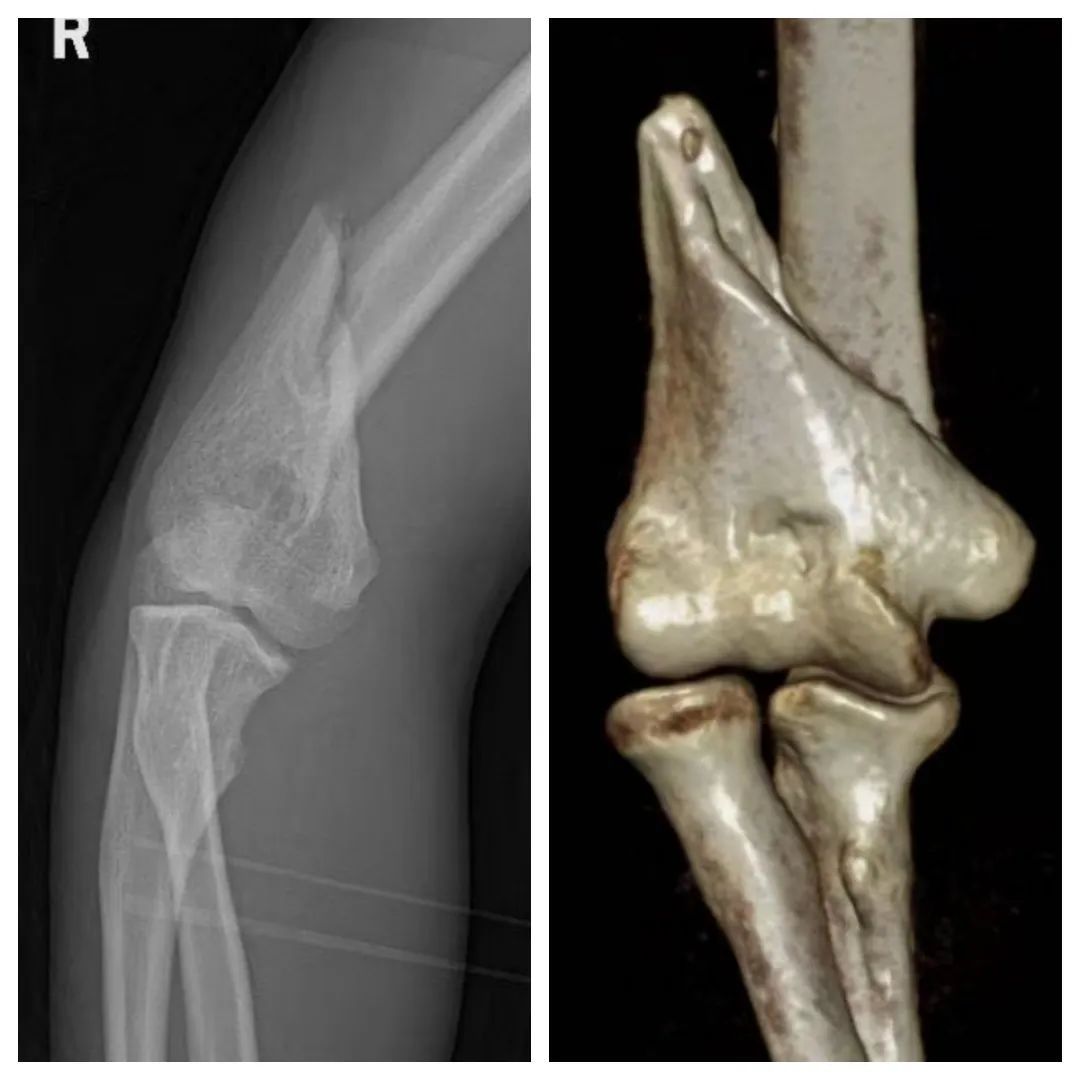

肱骨在近端为长圆管状的坚质骨,在中下1/3处逐渐变形为扁平状,在移行的交界区域,是肱骨骨骼结构的薄弱区域。同时叠加扳手腕时扭转力量的作用特点,所以绝大多数扳手腕导致的骨折类型是肱骨干中下1/3的螺旋型或斜型骨折;

除肱骨干骨折外,较常见的还有肱骨内上髁撕脱骨折,另外还有关于肩胛骨颈骨折、肩胛下肌断裂、肘关节内侧副韧带断裂、肘关节前脱位伴或不伴鹰嘴骨折、鹰嘴骨折、桡骨头前脱位或骨折脱位、桡骨干骨折、复发性半脱位的罕见报道。